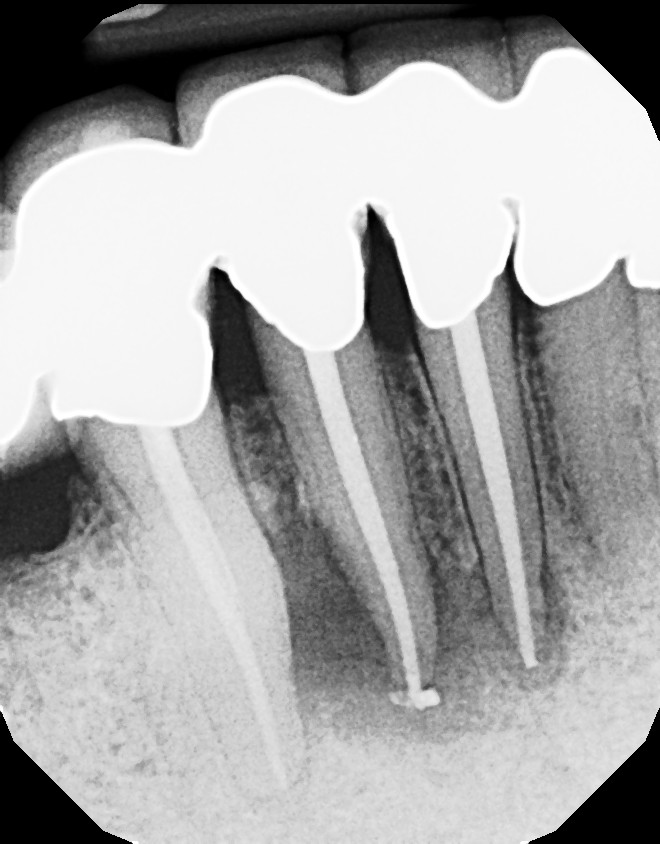

This is a multiple tooth / root issue that developed over time (4-5 years) under crowns where the nerves died and caused infection. After 3 months, bone regeneration (healing) occurred where infection was initially present. Endodontists (root canal specialists) are an important part of dental care for diagnosing and treating root issues.